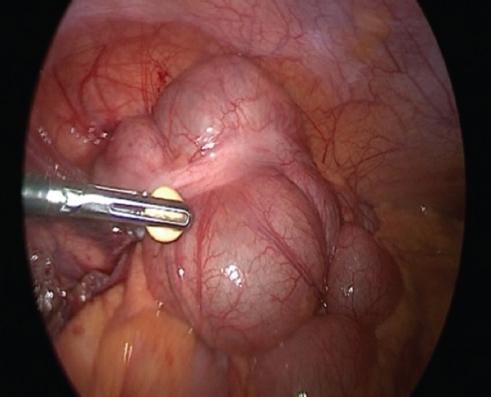

Cirugía realizada: apendicectomía laparoscópica. Abordaje con técnica de Hasson a través de una incisión umbilical de 1 cm, posteriormente se coloca un trocar umbilical de 12 mm y se inicia capnoperitoneo hasta 12 mmHg. Se introduce una lente de 30° y se realiza laparoscopia diagnostica. Se procede a la colocación de trocares de 5 mm, de región suprapúbica y de flanco izquierdo.

Hallazgos: adherencias laxas del epiplón a la pared. Líquido libre purulento de aproximadamente 20 ml. Apéndice vermiforme de 10 cm, hiperémico, edematoso en toda su extensión, con placas fibrinopurulentas. Se realiza apendicectomía y se maneja el muñón con técnica de Halsted. Sin complicaciones, con sangrado mínimo (Figs. 2 and 3).